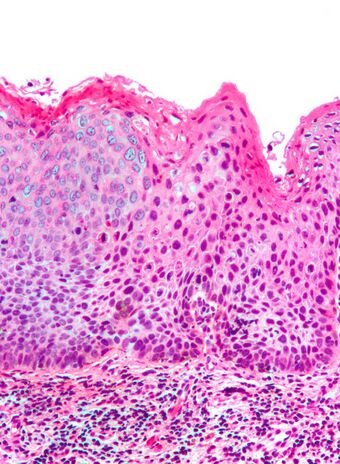

Micrograph of vulvar intraepithelial neoplasia III. H&E stain.

Micrograph of differentiated vulvar intraepithelial neoplasia. H&E stain.